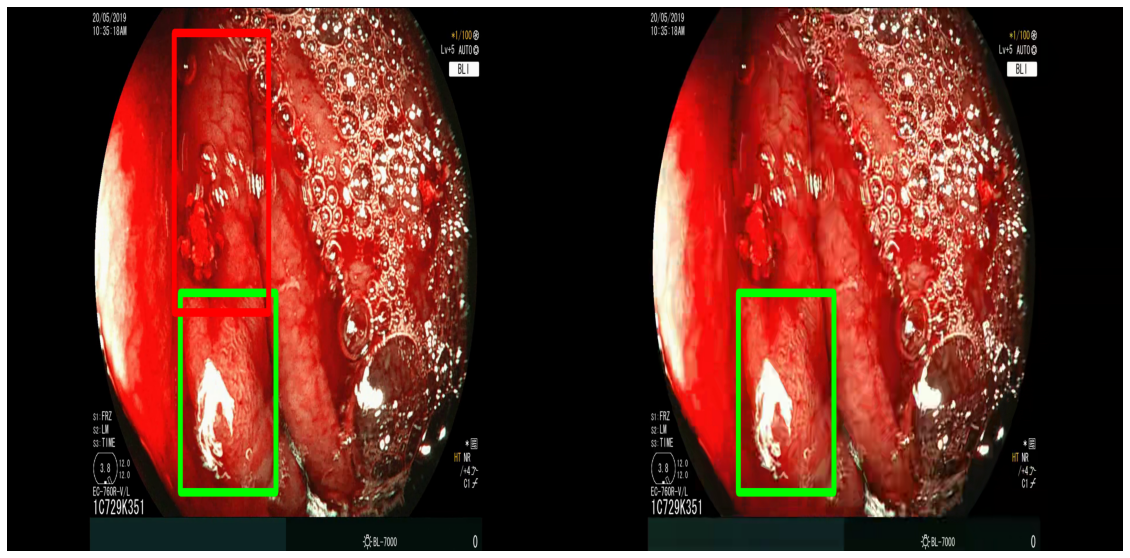

Compression quality: Figure 1 (middle) shows the compression rate versus frame quality distribution for H264 and HEVC. Importantly, we see that H264 and HEVC compress the most medically relvant frames statistically significantly worse: treating each QP value separately, a two-sided Kolmogorov-Smirnov test between distribution of PSNR-CbCr shows that the frame quality is lower for polyp frames than for all frames. For each QP value, , , H264 (HEVC) maximum p-value over all tests is (), mean test statistic (). For the same test with PSNR-Y, see the Appendix. Figure 2 top two rows show the lowest quality compressed frames inside the body according to PSNR-CbCr, with and without polyps (for the absolute worst quality compressed frames, see the Appendix).

A.3 Lowest quality compressed frames